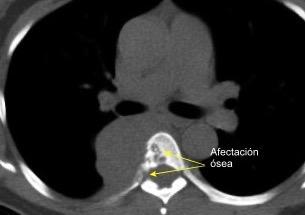

59. CUERPO VERTEBRAL. AFECTACIÓN CON MASA

60. DENSIDAD ÓSEA. PERDIDA DE

32 años .Preeclampsia a los 19. Hipertensión no controlada. Masa paravertebral sólida que se realza intensamente con afectación ósea.

Yue Y t al. Asymptomatic left posterior mediastinal functional Paraganglioma. A case report. Medicine . 2019